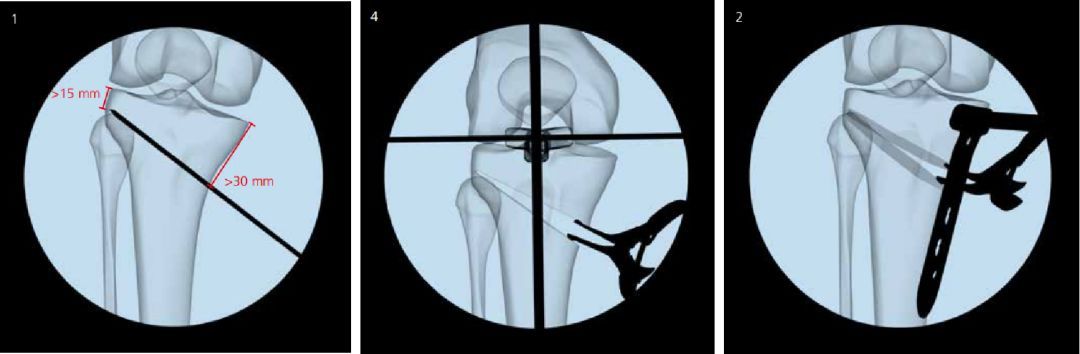

截骨矫形手术

对于年龄小于65岁、膝关节活动度正常、韧带功能正常、下肢力线不良(膝内翻与膝外翻)、关节外畸形的患者,可以进行截骨矫形手术,能有效减少内侧的关节面负重和接触面积,从而延缓关节炎进一步加重。